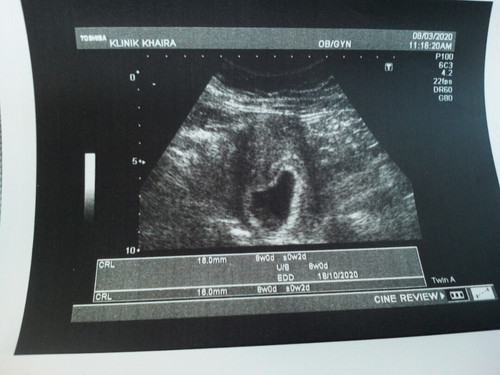

8w2d

td sy pg scan & syukur da blh nmpk heartbeat wlpn msh kecil?ada x mommies yg sma mcm sy yg tgn prgnt skrg tp ank last masih bf wlpn da berumur 2y3m?dktr ckp xbgs juga sbb blh mnyebabkn keguguran sbb hormon kita da brubahkn..